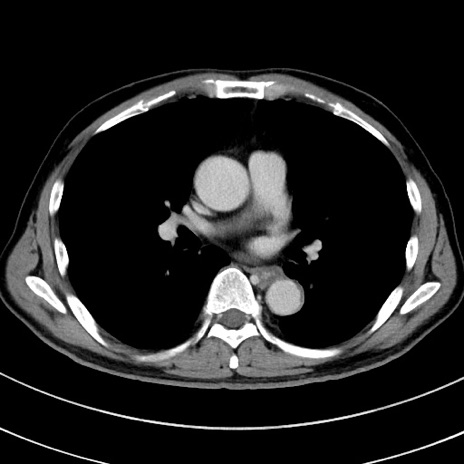

症例8(横断像)

【症例】 60歳代男性

【主訴】 黒色吐物

【現病歴】 4日前から嘔気自覚、2日前の朝食後にも嘔気あり、自分で手で嘔吐反射起こし嘔吐したところ血が混ざっていたため受診。

【既往歴】 5年前汎発性腹膜炎を伴う急性虫垂炎で手術、高血圧、前立腺肥大症、高脂血症

【身体所見】 腹部正中に手術癩痕あり 腹部平坦・軟圧痛なし膨満感あり

【データ】WBC 8400、CRP 4.54